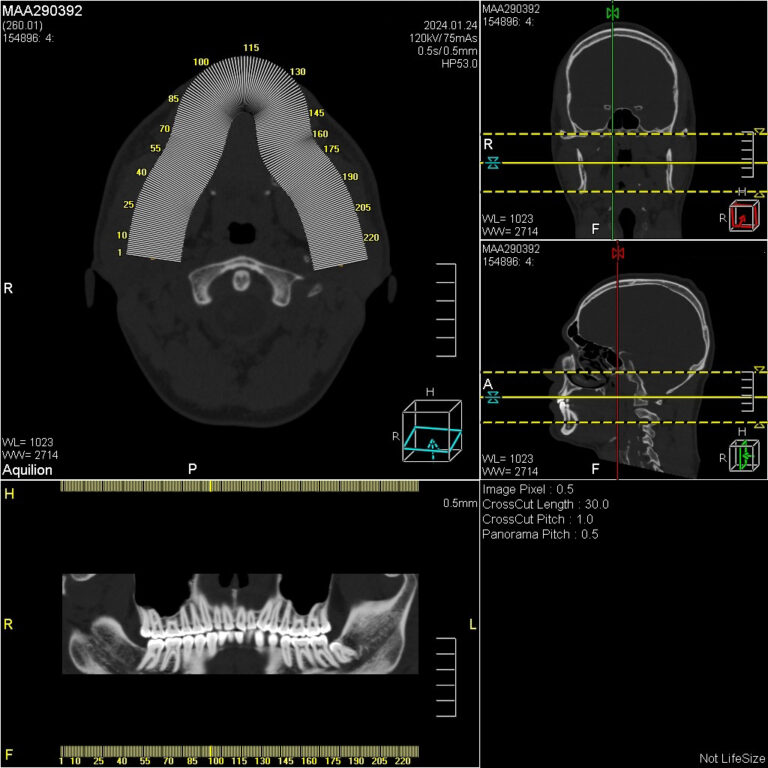

Мультиспиральная дентальная компьютерная томография (МДКТ или, как ее еще называют, КТ зубов) – это современный высокоточный метод лучевой диагностики, с помощью которого получают объемные цифровые изображения всей зубочелюстной системы. В основе метода лежит применение рентгеновского излучения и последующая цифровая обработка полученных данных специальными компьютерными программами.

Мультиспиральный томограф выполняет послойное сканирование области верхней и нижней челюстей с помощью рентгеновских лучей, а затем, используя компьютерную обработку данных, создает 3D-модели исследуемой зоны. Современные модели томографов проводят круговое сканирование по спирали, делая срезовые снимки на расстоянии 0,5 мм друг от друга. Затем на основе этих данных реконструируются детальные изображения челюстно-лицевой области в трехмерном формате.

В отличие от конусно-лучевой компьютерной томографии (КЛКТ), которая также в последнее время применяется в стоматологии, МДКТ помогает лучше визуализировать костные структуры на фоне артефактов от имплантов и протезов, выполнить сканирование быстрее, без двигательных артефактов, в любом объеме под запрос вашего ортодонта.

- Информативность. Дентальная КТ позволяет обнаружить признаки патологии, которые не видны на обычных (2D) панорамных снимках – ортопантомограммах. На двухмерных рентгенограммах различные структуры накладываются друг на друга. В отличие от этого пространственные модели дают возможность рассмотреть челюстно-лицевой аппарат в различной проекции и плоскости.

- Широкие возможности диагностики. На трехмерных изображениях можно увидеть в целом верхнюю и нижнюю челюсть, включая гайморовы пазухи, височно-нижнечелюстные суставы. Помимо костной ткани при проведении КТ можно оценить состояние окружающих мягких тканей. Это бывает особенно важно при выборе оптимального способа протезирования и имплантации, при подозрении на опухолевые процессы, при планировании оперативного вмешательства.

Исследование занимает всего пару минут. Данные, полученные при сканировании, проходят цифровую обработку и выводятся на монитор компьютера в виде 3D-изображений. Врач-рентгенолог внимательно анализирует данные и выдает заключение.